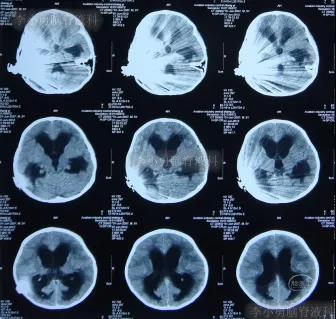

一到第3家医院,就开展了急诊气管插管和之后呼吸机辅助呼吸的抢救。住院次日,即2012年5月17日,脑CT检查并未发现明显异常(图-3)。

图-3:2012年5月17日耳蜗植入术后状态脑CT

在利奈唑胺、头孢吡肟、利福平等药物抗炎治疗2周后,发热症状逐渐得到控制,意识也开始转清醒,但患儿自己示意有头痛症状;因腰穿未能抽出脑脊液,所以给予甘露醇处理,之后头痛可有缓解。在住院11天时即2012年5月27日(图-4)和住院14天时即2012年6月1日(图-5),分别进行过脑CT的检查,显示脑室有逐渐扩大的表现,但因为病情有所缓解,所以给以继续密切观察的处理。

图-4:2012年5月27日脑CT脑室稍扩大

图-5:2012年6月1日脑CT脑室稍扩大

但是在住院第19天即在2012年6月6日时(注:即在人工耳蜗植入术颅内感染并发症21天时),患儿出现了左眼闭合和右侧肢体瘫痪即交叉性偏瘫,以及进食无力和不能交流的病情加重的表现,立即脑CT检查发现了脑积水的表现(图-6)。

图-6:2012年6月6日脑CT脑室扩大显著

入院当天脑CT检查发现,脑积水又有加重表现(图-8)。

图-8:2012年6月7日脑CT脑积水加重